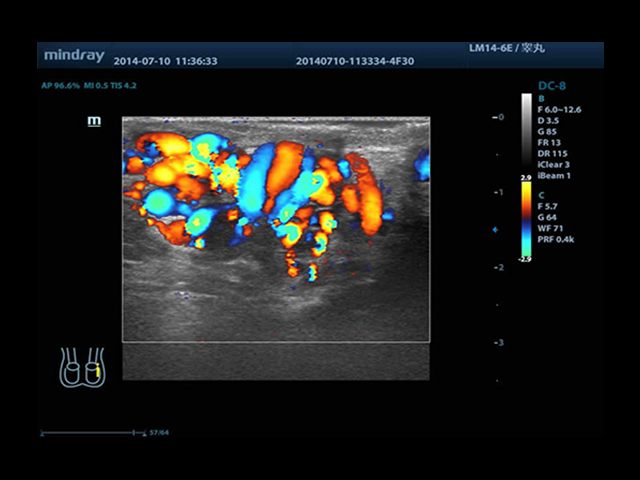

Mindray DC-8 Exp оснащен новым поколением датчиков с увеличенным количеством элементов и инновационной технологией "3T". Это позволяет достичь высокой детализации и качества изображения. Благодаря новейшей технологии iFlow, можно визуализировать даже самые мелкие сосуды и кровеносные пути.

• HR-flow™ - режим отображения кровотока с высоким временным и пространственным разрешением для точной и однородной визуализации сосудов, в том числе самых мелких

• Natural Touch Elastography - опция оценки эластичности ткани (эластография), с программой анализа. Действует на линейных и внутриполостных датчиках. Компрессионный метод.